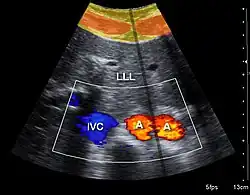

Doppler ultrasonography is used to study blood flow and muscle motion. The different detected speeds are represented in color for ease of interpretation, for example leaky heart valves: the leak shows up as a flash of unique color. Colors may alternatively be used to represent the amplitudes of the received echoes.

Doppler ultrasonography

Doppler ultrasonography employs the Doppler effect to assess whether structures (usually blood)[58][61] are moving towards or away from the probe, and their relative velocity. By calculating the frequency shift of a particular sample volume, flow in an artery or a jet of blood flow over a heart valve, its speed and direction can be determined and visualized, as an example. Color Doppler is the measurement of velocity by color scale. Color Doppler images are generally combined with gray scale (B-mode) images to display duplex ultrasonography images.[62] Uses include: